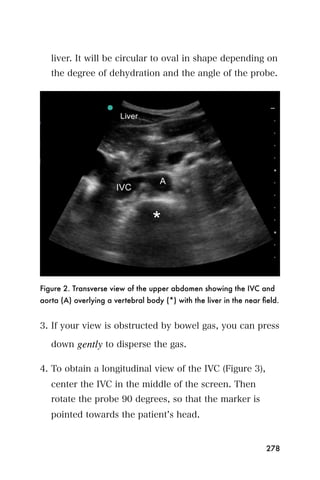

2. Scan the heart from the subxyphoid, parasternal, and

apical views to determine if a pericardial effusion is

present and if there are findings suggestive of cardiac

tamponade.

3. Determine where the pericardial effusion is largest